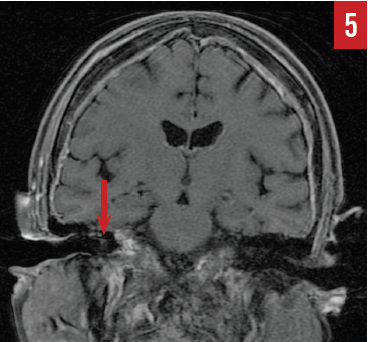

MR imaging of the brain (Figures 4 and 5) identified diffuse epidural enhancement, as well as enhancement in the right internal auditory canal. Inasmuch as this patient was on low-dose prednisone for temporal arteritis, intratympanic steroid treatment was utilized but brought about no improvement in hearing acuity.

Figure 5. Coronal MR imaging showing slight enhancement within the right internal auditory canal, likely secondary to epidural disease (case report 2).